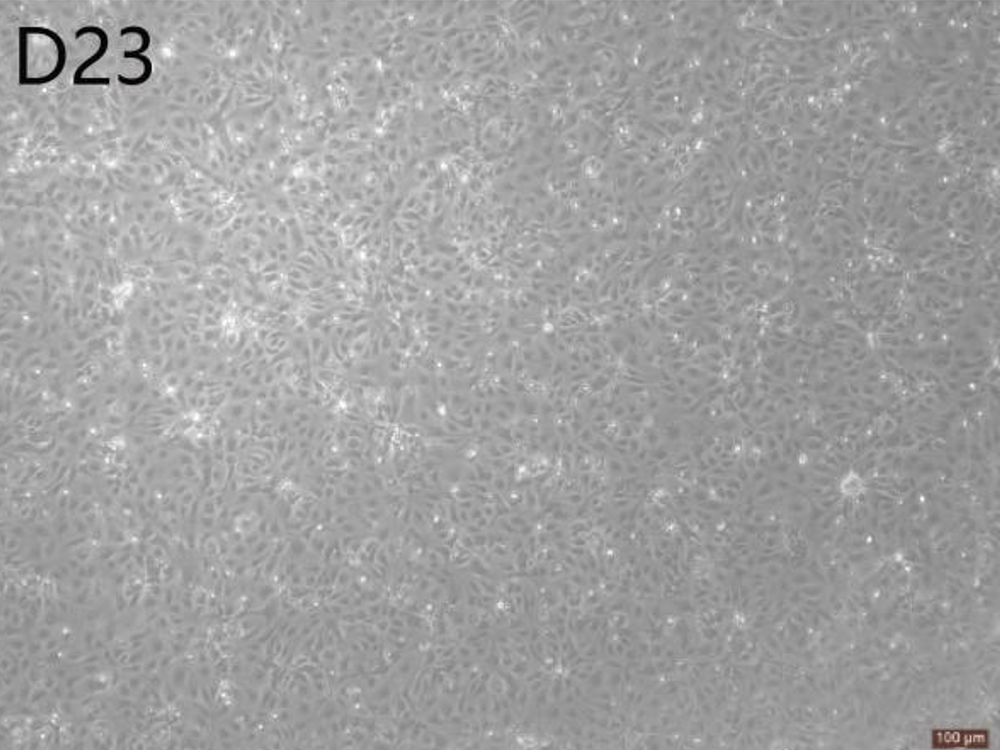

Renal podocyte-like cells are similar to in vivo podocytes in morphological characteristics and express podocyte-specific markers, such as Podocin (glomerular podocyte transmembrane protein), Synaptopodin (actin-related protein in podocytes and dendritic spines), and WT-1 (Wilm's Tumor Protein), with a purity higher than 90%. This product can be widely used in basic research, drug development, clinical translational research and other fields